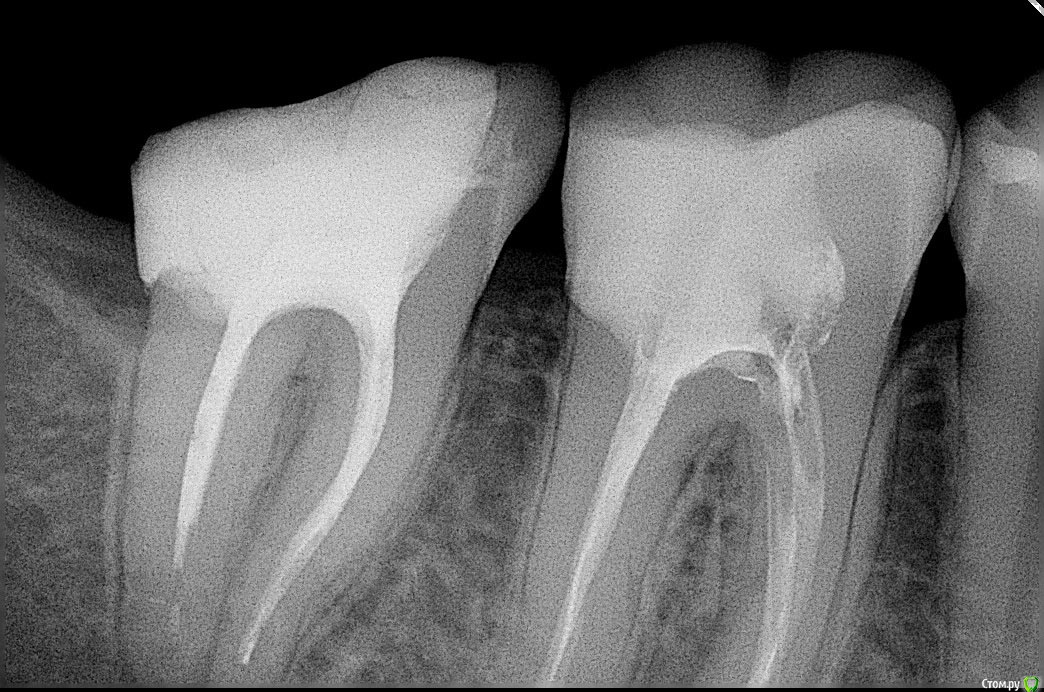

Didi Опубликовано 30 декабря, 2016 Поделиться Опубликовано 30 декабря, 2016 (изменено) После пломбировки 6-го зуба снизу он болел при накусывании один или два месяца.Спустя 6 лет после пломбировки, после регулярной чистки между зубами толстой нитью (раньше там не чистил), на следующий день этот зуб начал снова болеть при накусывании и шатании. Как только прекращаю чистить между зубами толстой нитью, боль при накусывании проходит через 2-3 дня. Наверное происходит давление на зуб при вытаскивании нити, из за которого он начинает болеть на следующий день. В других зубах с запломбироваными каналами после чистки между ними болей нет. Другие зубы в отличии от этого после пломбировки болели максимум неделю.В болящем зубе есть стекловолоконный штифт. (может дело в нём?)Зуб запломбирован жидкой гуттаперчей B-sustem.Пломбировала стоматолог женщина. На снимках болит зуб тот что справа. Посмотрите пожалуйста прямо сейчас.ВопросНормально ли то что зуб болел после пломбировки 1-2 месяца, а спустя 6 лет начинает болеть после чистки толстой нитю между зубами, на следующий день? Если нет то в чём скорей всего причина и что делать?Буду благодарен Вам за помощь Изменено 30 декабря, 2016 пользователем Didi Ссылка на комментарий

dok1 Опубликовано 30 декабря, 2016 Поделиться Опубликовано 30 декабря, 2016 Пломбирование каналов обоих зубов оставляет желать лучшего. Бегом к врачу перелечивать. Ссылка на комментарий

Didi Опубликовано 31 декабря, 2016 Автор Поделиться Опубликовано 31 декабря, 2016 (изменено) С левым зубом всё понятно, там не до конца канал запломбирован.А как понять что правый плохо запломбирован?Слышу об этом впервые. Изменено 31 декабря, 2016 пользователем Didi Ссылка на комментарий

dok1 Опубликовано 31 декабря, 2016 Поделиться Опубликовано 31 декабря, 2016 Там в правом на снимке корне два канала. Приглядитесь. И пористо всё запломбировано. Ссылка на комментарий

red_butler Опубликовано 1 января, 2017 Поделиться Опубликовано 1 января, 2017 По снимку похоже нет нормального контактного пункта. Зубы требуют протезирования. Седьмой перелечит. По поводу шестого я не так категоричен. Ссылка на комментарий

St. Опубликовано 3 января, 2017 Поделиться Опубликовано 3 января, 2017 red_butler По поводу шестого я не так категоричен. +1. По снимку все приемлемо.Но если выяснится что точно болит этот зуб а не десна, то да - придется переделывать в нем каналы. 1 Ссылка на комментарий